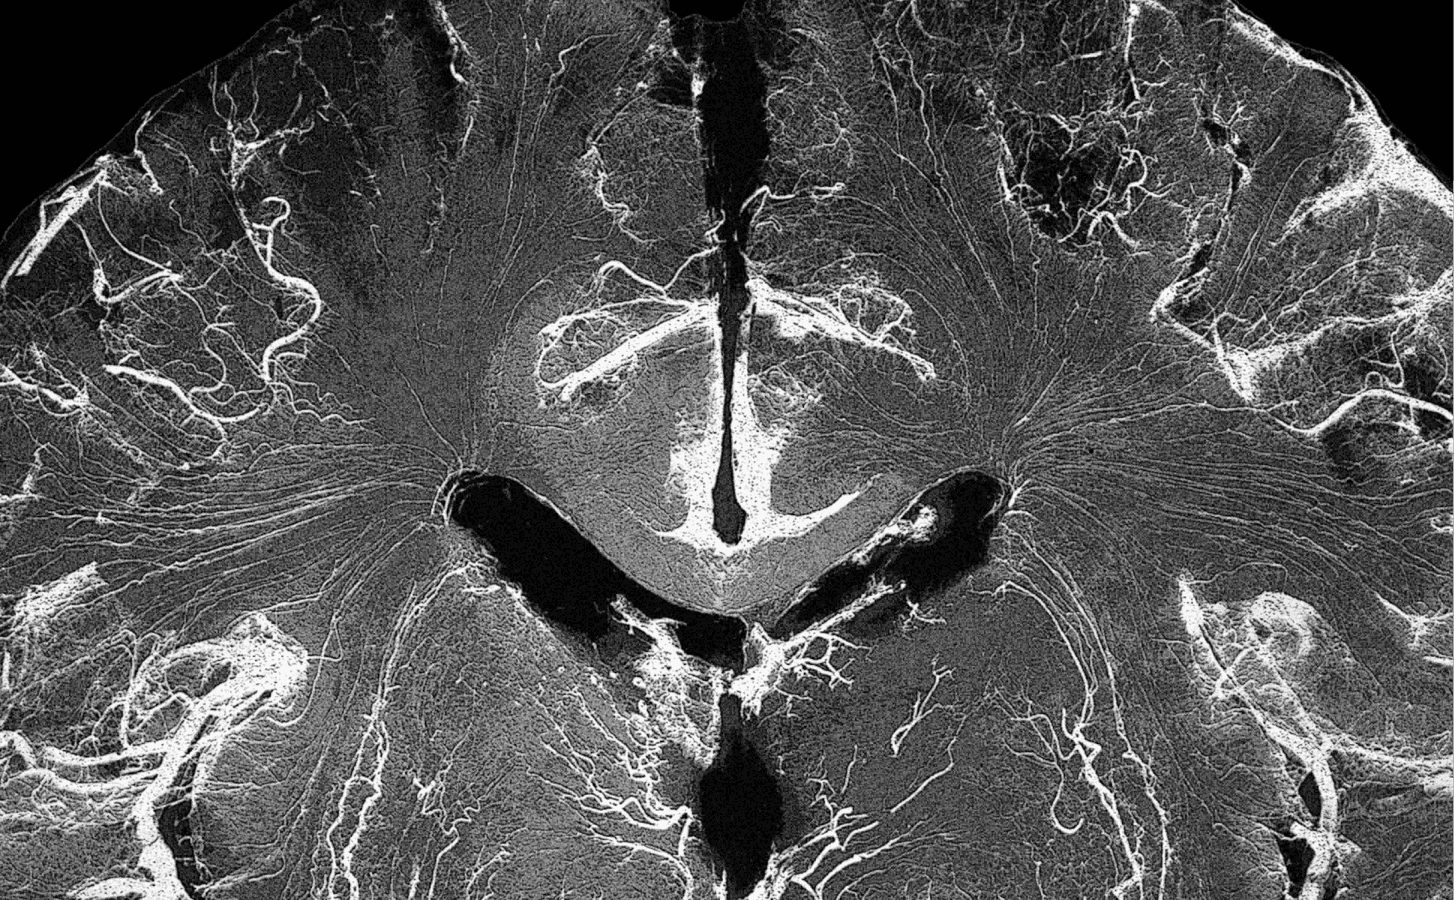

Think about stories like Neuralink in the news or even movies where minds link with machines. Merge Labs is taking a fresh approach without surgery, using ultrasound and engineered proteins to read and write neural signals. You've probably noticed how BCI tech is evolving fast, and this feels like the next natural step.

Engineered proteins are custom-designed molecules. For Merge Labs' approach, these proteins help make brain cells sensitive to non-invasive signals, so the system can read or influence neural activity safely from outside the skull.

A BCI is tech that lets your brain communicate directly with computers, reading thoughts or signals to control things. Merge Labs focuses on non-invasive methods, meaning no surgery, just external ways like ultrasound to interact with neurons. It's like giving AI a window into how we think without opening the door.